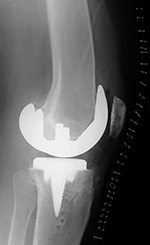

Unicompartmental knee prosthesis placed in the medial compartment (lateral view) |

| From Taljanovic, 2005 |